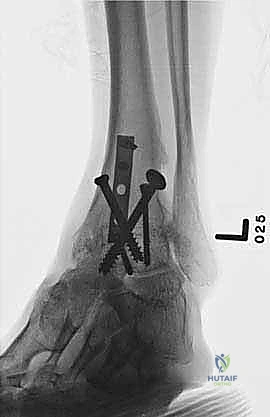

| طرق العلاج | أدوية مضادة للالتهابات (NSAIDs)، أحذية طبية مخصصة (Rocker-bottom shoes)، دعامات الكاحل (AFO)، حقن الكورتيزون أو البلازما (PRP)، العلاج الطبيعي. | جراحة إزالة الغضاريف التالفة ودمج العظام (Arthrodesis) باستخدام مسامير وألواح معدنية. |

- رؤية ممتازة للمفصل: يوفر المدخل الأمامي رؤية بانورامية واسعة ومباشرة لكامل السطح المفصلي للظنبوب وعظم الكاحل، مما يسمح بإزالة الغضاريف التالفة بدقة متناهية.

- تصحيح التشوهات بدقة: يسمح هذا المدخل بتعديل انحرافات الكاحل (سواء كان يميل للداخل Varus أو للخارج Valgus) وإعادته إلى المحور الميكانيكي الطبيعي للساق.

- الحفاظ على عظم الشظية (Fibula): على عكس المدخل الجانبي الذي يتطلب غالباً قطع عظم الشظية، يحافظ المدخل الأمامي على الشظية سليمة، مما يحافظ على العرض الطبيعي للكاحل ويحمي الأربطة الجانبية.

- تثبيت ميكانيكي حيوي أقوى: يتيح المدخل الأمامي وضع شريحة معدنية (Anterior Plate) على الجانب الأمامي للمفصل. من الناحية الميكانيكية الحيوية (Biomechanics)، يعتبر الجانب الأمامي هو "جانب الشد" (Tension side) أثناء المشي. وضع الشريحة هنا يوفر تثبيتاً فائق القوة ويقلل من معدلات عدم الالتئام.

- التخطيط الجراحي الرقمي: باستخدام صور الأشعة المقطعية، يقوم الدكتور هطيف بتخطيط الجراحة على الكمبيوتر لاختيار حجم المسامير والشرائح المناسبة بدقة مليمترية.

خطوات جراحة تثبيت مفصل الكاحل الأمامي بالتفصيل (Step-by-Step Surgical Procedure)

تُجرى العملية تحت التخدير العام أو النصفي (الشوكي)، وتستغرق عادةً بين ساعتين إلى ثلاث ساعات، وتتطلب دقة ومهارة فائقتين. إليكم الخطوات الجراحية كما ينفذها الأستاذ الدكتور محمد هطيف:

1. الوضعية والشق الجراحي (Positioning and Incision)

يستلقي المريض على ظهره (Supine position). يتم استخدام عاصبة (Tourniquet) حول الفخذ لتقليل النزيف وتوفير رؤية واضحة. يقوم الدكتور هطيف بإجراء شق طولي أمامي فوق مفصل الكاحل، عادة بين وتر العضلة الظنبوبية الأمامية (Tibialis Anterior) ووتر العضلة الباسطة الطويلة لإصبع القدم